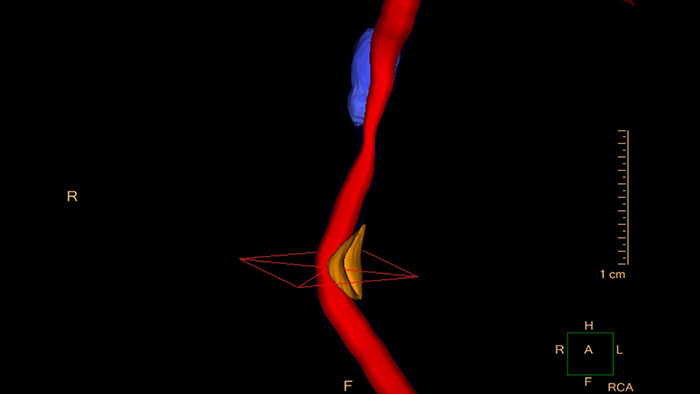

One-click 3D calcium segmentation

One-click 3D segmentation and quantification for coronary arteries calcifications including mass, Agatston, and volume scores.

Evaluate coronaries plaque

Enables performing cross-sectional measurements along the coronary arteries, and automatically calculates regional and global quantities of plaque volume.